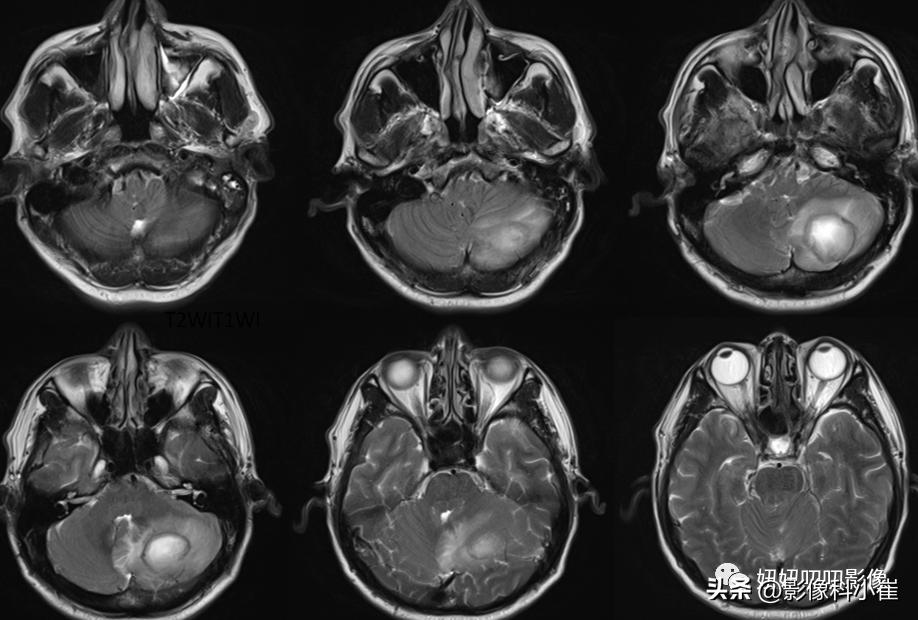

左侧小脑半球片状长短T1等长T2 异常信号,边界不清,大小约3.2X2.9X2.4cm,T2-Flair呈等高信号,周围见斑片状水肿带,DWI 示病变明显弥散受限,增强扫描可见不均匀环状强化。双侧放射冠、皮层下另见少许斑点状等长 T1、长T2 异常信号灶,T2 Flair 呈高信号,DWI未见明显弥散受限,增强扫描未见明显异常强化。第四脑室受压变窄,幕上脑室系统未见明显扩张。脑沟、脑裂略增宽。中线结构无移位。双侧筛窦、上领窦粘膜增厚。